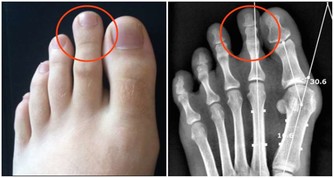

在堅硬地上所有劇烈運動,比如下蹲、蛙跳、跑步、跳繩還有跳舞,都會加重對膝蓋骨的磨損。尤其是蹲下去再站起來,對關節的磨損最大。關節軟骨大概有1到2毫米,作用就是緩沖壓力,保護骨骼不破裂。

它就相當於跑道上的橡膠,能夠幫助我們緩衝上下運動時的一個力,進而來保護我們的關節。如果非要在堅硬地板上運動,在超強的反作用力下彈回來,對關節和骨骼的損傷相當大。因此,建議只在橡膠運動場地做運動。

在爬山和爬樓梯的時候,膝關節會承受超過本身體重3到4倍的壓力。尤其是50歲以後,人的膝關節多少都會有些磨損的情況,此時,就要減少此類運動。對於有些有過膝關節損傷的朋友40歲以後就要特別注意了。